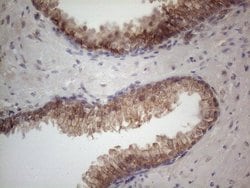

MTF1 Monoclonal Antibody for Western Blot, IHC (P)

| Immunohistochemistry (Paraffin), Western Blot | |